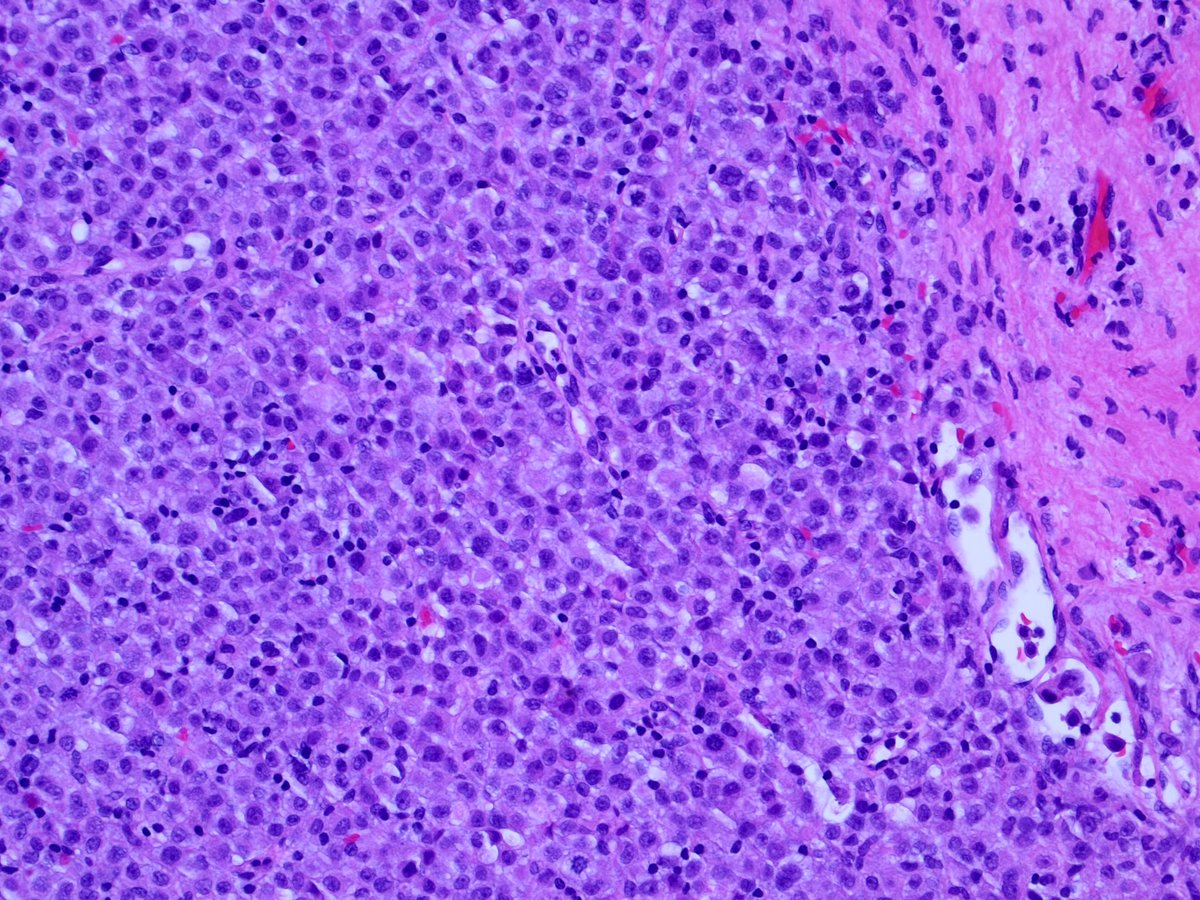

1. Discussion: Interesting voting trend. “Benign” held the early slight majority, then some astute people suggested metastatic lobular carcinoma. The voting them swung decidedly towards “cancer”!

6. Some annotated images showing the atypical features of the red box cells above.

None of these are specific; histiocytes may resemble lobular cancer cells. However, taken together, these atypical features should raise concern for malignancy, and prompt a frozen section.